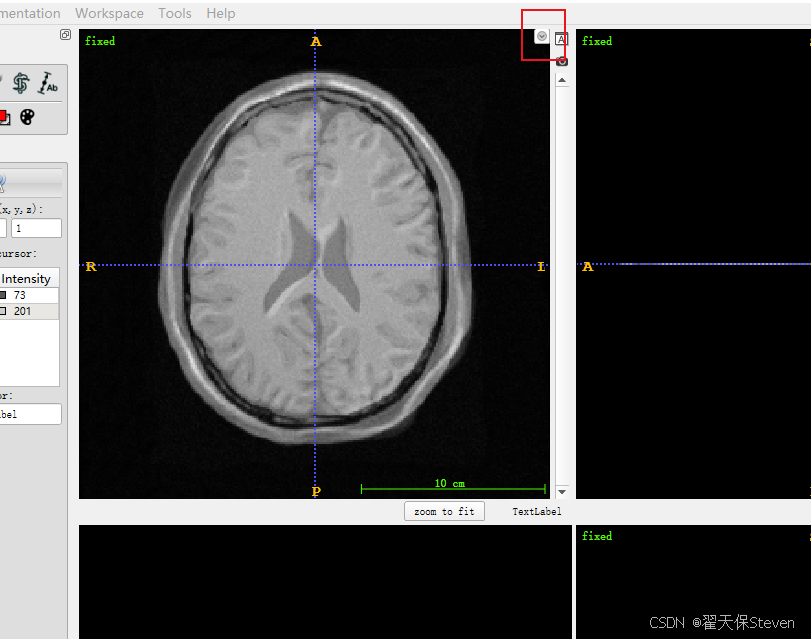

3)加载fixed.mhd成功如下所示。

4)点击File,点击Add Another Image,加载moving.mhd,如下所示。

5)在第二张图右上角有个箭头,点一下,选择Display as overlay,会发现第二张图像和第一张图像融合在一起了。